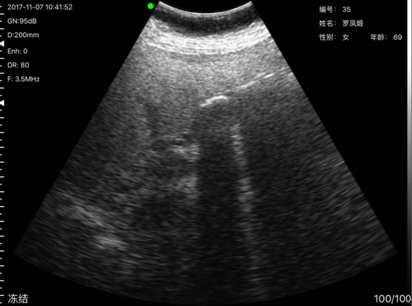

病例7,姓名:罗x姬,性别:女,年龄69岁,发现其胆囊有两亮点疑似胆囊结石,后经上级医院复查确诊为胆囊结石。